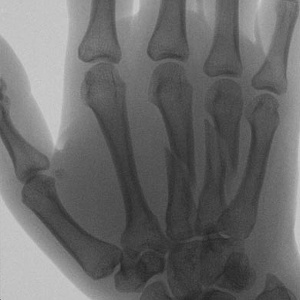

Example X-Ray Images

Oblique Metacarpal Fractures